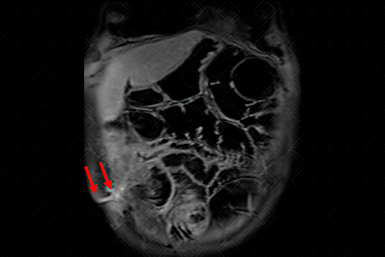

Texto alternativo para a imagem Figura 2. Créditos: Dra. Elazir Mota - Rio de Janeiro/RJ

Descrição da figura 2: Na sequência VIBE 3D pós-contraste plano coronal (ponderada em T1), observamos trajeto fistuloso (setas vermelhas) que se estende da alça doente à parede abdominal.